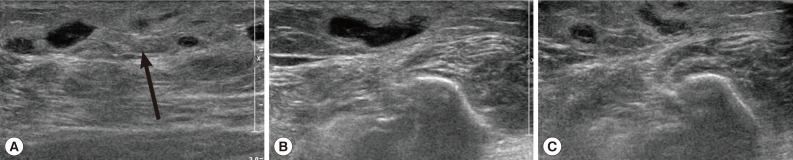

Routine laboratory tests were unremarkable, and no eosinophilia was noted. Ultrasonography (USG) showed diffuse longitudinal (about 10 cm) thickening of the subcutaneous fat layer with increased echogenicity on the lateral aspect of the right fibula (Fig. 1A). The subcutaneous thickening was located around the region where the Achilles tendon of the right lower leg begins. A long tubular structure with a diameter of 3-5 mm was found inside the subcutaneous thickening (Fig. 1B). The tubular structure was mostly continuous without interruption and partially filled with echogenic material (Fig. 1B). The anteroinferior aspect of the lesion was isolated tubular-shaped whereas the posterosuperior aspect was a tubular cystic lesion having a blind loop (Fig. 1C). These findings could be interpreted as partially thrombosed venous structure surrounded by thrombophlebitic inflammatory changes. However, in this case, venous structures of the lesion were normal and accompanied by an isolated cystic lesion. Thus, this case was suggested as a recurred sparganosis by a remained plerocercoid worm or possibly due to incomplete removal of the scolex at the time of the previous operation.